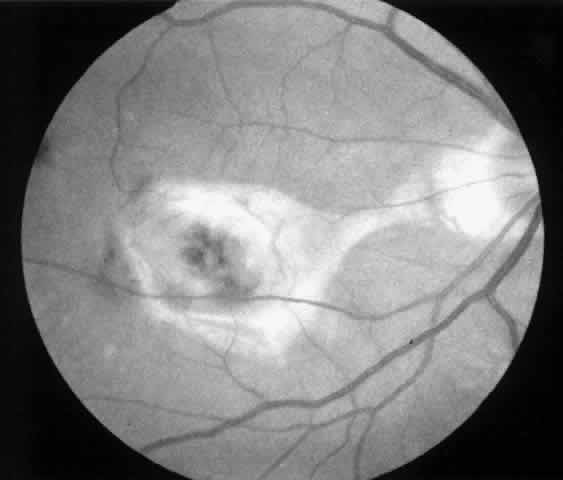

3. A 39-year-old patient with POHS developed a recurrent choroidal neovascular membrane involving the fovea with a decrease in vision to 20/100 (6/30) (Fig. 11). He underwent surgical excision but laser was not applied to the retinotomy site at the conclusion of the case. One month after surgery his vision improved to 20/30 (6/9) and the retinotomy was not noticeable (Fig. 12).

Fig. 11. Preoperative photograph of a 39-year-old patient with presumed ocular histoplasmosis syndrome (case 3). Visual acuity is 20/100 (6/30).

Fig. 12. Postoperative photograph (case 3). One month after surgery visual acuity is 20/30 (6/9). Retinotomy site is not noticeable.